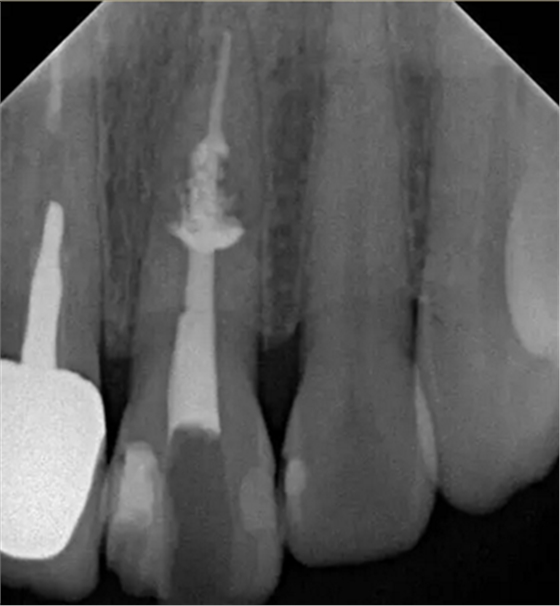

診斷:左上中切牙牙根內(nèi)吸收。治療計(jì)劃:左上中切牙根管治療,全冠修復(fù)。 治療過程:患者知情同意。使用含1/100,000腎上腺素的4%鹽酸阿替卡因(碧蘭麻,艾龍)局部浸潤麻醉,橡皮障隔濕。去腐未盡露髓,露髓孔出血多。開髓,使用10#不銹鋼K銼(MANI,日本)探查根管,根管中段有鈣化物阻擋,不能達(dá)到牙根全長(圖3A)。在顯微鏡下(Leica M400E,萊卡, 德國) 使用超聲尖(E1根管治療超聲尖,啄木鳥公司,中國)通開,采用根管長度測量儀(Root ZX, Morita公司,日本)加診斷絲片法(圖1B)測量根管長22 mm。使用控制扭矩馬達(dá)(X-smart,登士柏)和鎳鈦旋轉(zhuǎn)器械(Hero 642, Micromega)根管預(yù)備,根管預(yù)備過程中使用5.25%次氯酸鈉溶液沖洗。 根備完成后使用超聲蕩洗根管,5.25%次氯酸鈉溶液3 分鐘, 17% EDTA溶液1分鐘。干燥根管,使用螺旋充填器根管內(nèi)封氫氧化鈣糊,氧化鋅丁香油水門汀暫封。1周后患者復(fù)診,患者述無術(shù)后不適,檢查暫封完好,無叩痛,不松,牙齦無紅腫瘺管。使用橡皮障隔濕,去除暫封物,超聲蕩洗根管,5.25%次氯酸鈉溶液3 分鐘, 17% EDTA溶液1分鐘。干燥根管,牙膠尖(達(dá)雅鼎,中國)和必蘭根充糊劑(Cortisomol, 艾龍公司,法國)熱垂直加壓法根管充填。術(shù)后片顯示根充恰填,可見牙膠/糊劑被壓入鈣化物周圍和內(nèi)部縫隙內(nèi)

1月后復(fù)查無不適,行全瓷冠修復(fù)。8月2周后復(fù)查,患者無不適主訴,牙冠美觀,邊緣完好,患牙無叩痛,不松動(dòng),牙齦無紅腫瘺管, X線片示根周膜連續(xù),根尖周未見異常。建議患者避免用前牙撕咬食物,定期復(fù)查。 討論: 臨床上,由于牙根內(nèi)吸收和牙根外吸收的治療方法和預(yù)后不同,常需要對兩者進(jìn)行鑒別診斷。過去通常采用偏移投照的方法鑒別兩者。在偏移投照片上,外吸收病損和根管輪廓相對位置較正位片會(huì)發(fā)生變化,而內(nèi)吸收病損則不會(huì)[12]。